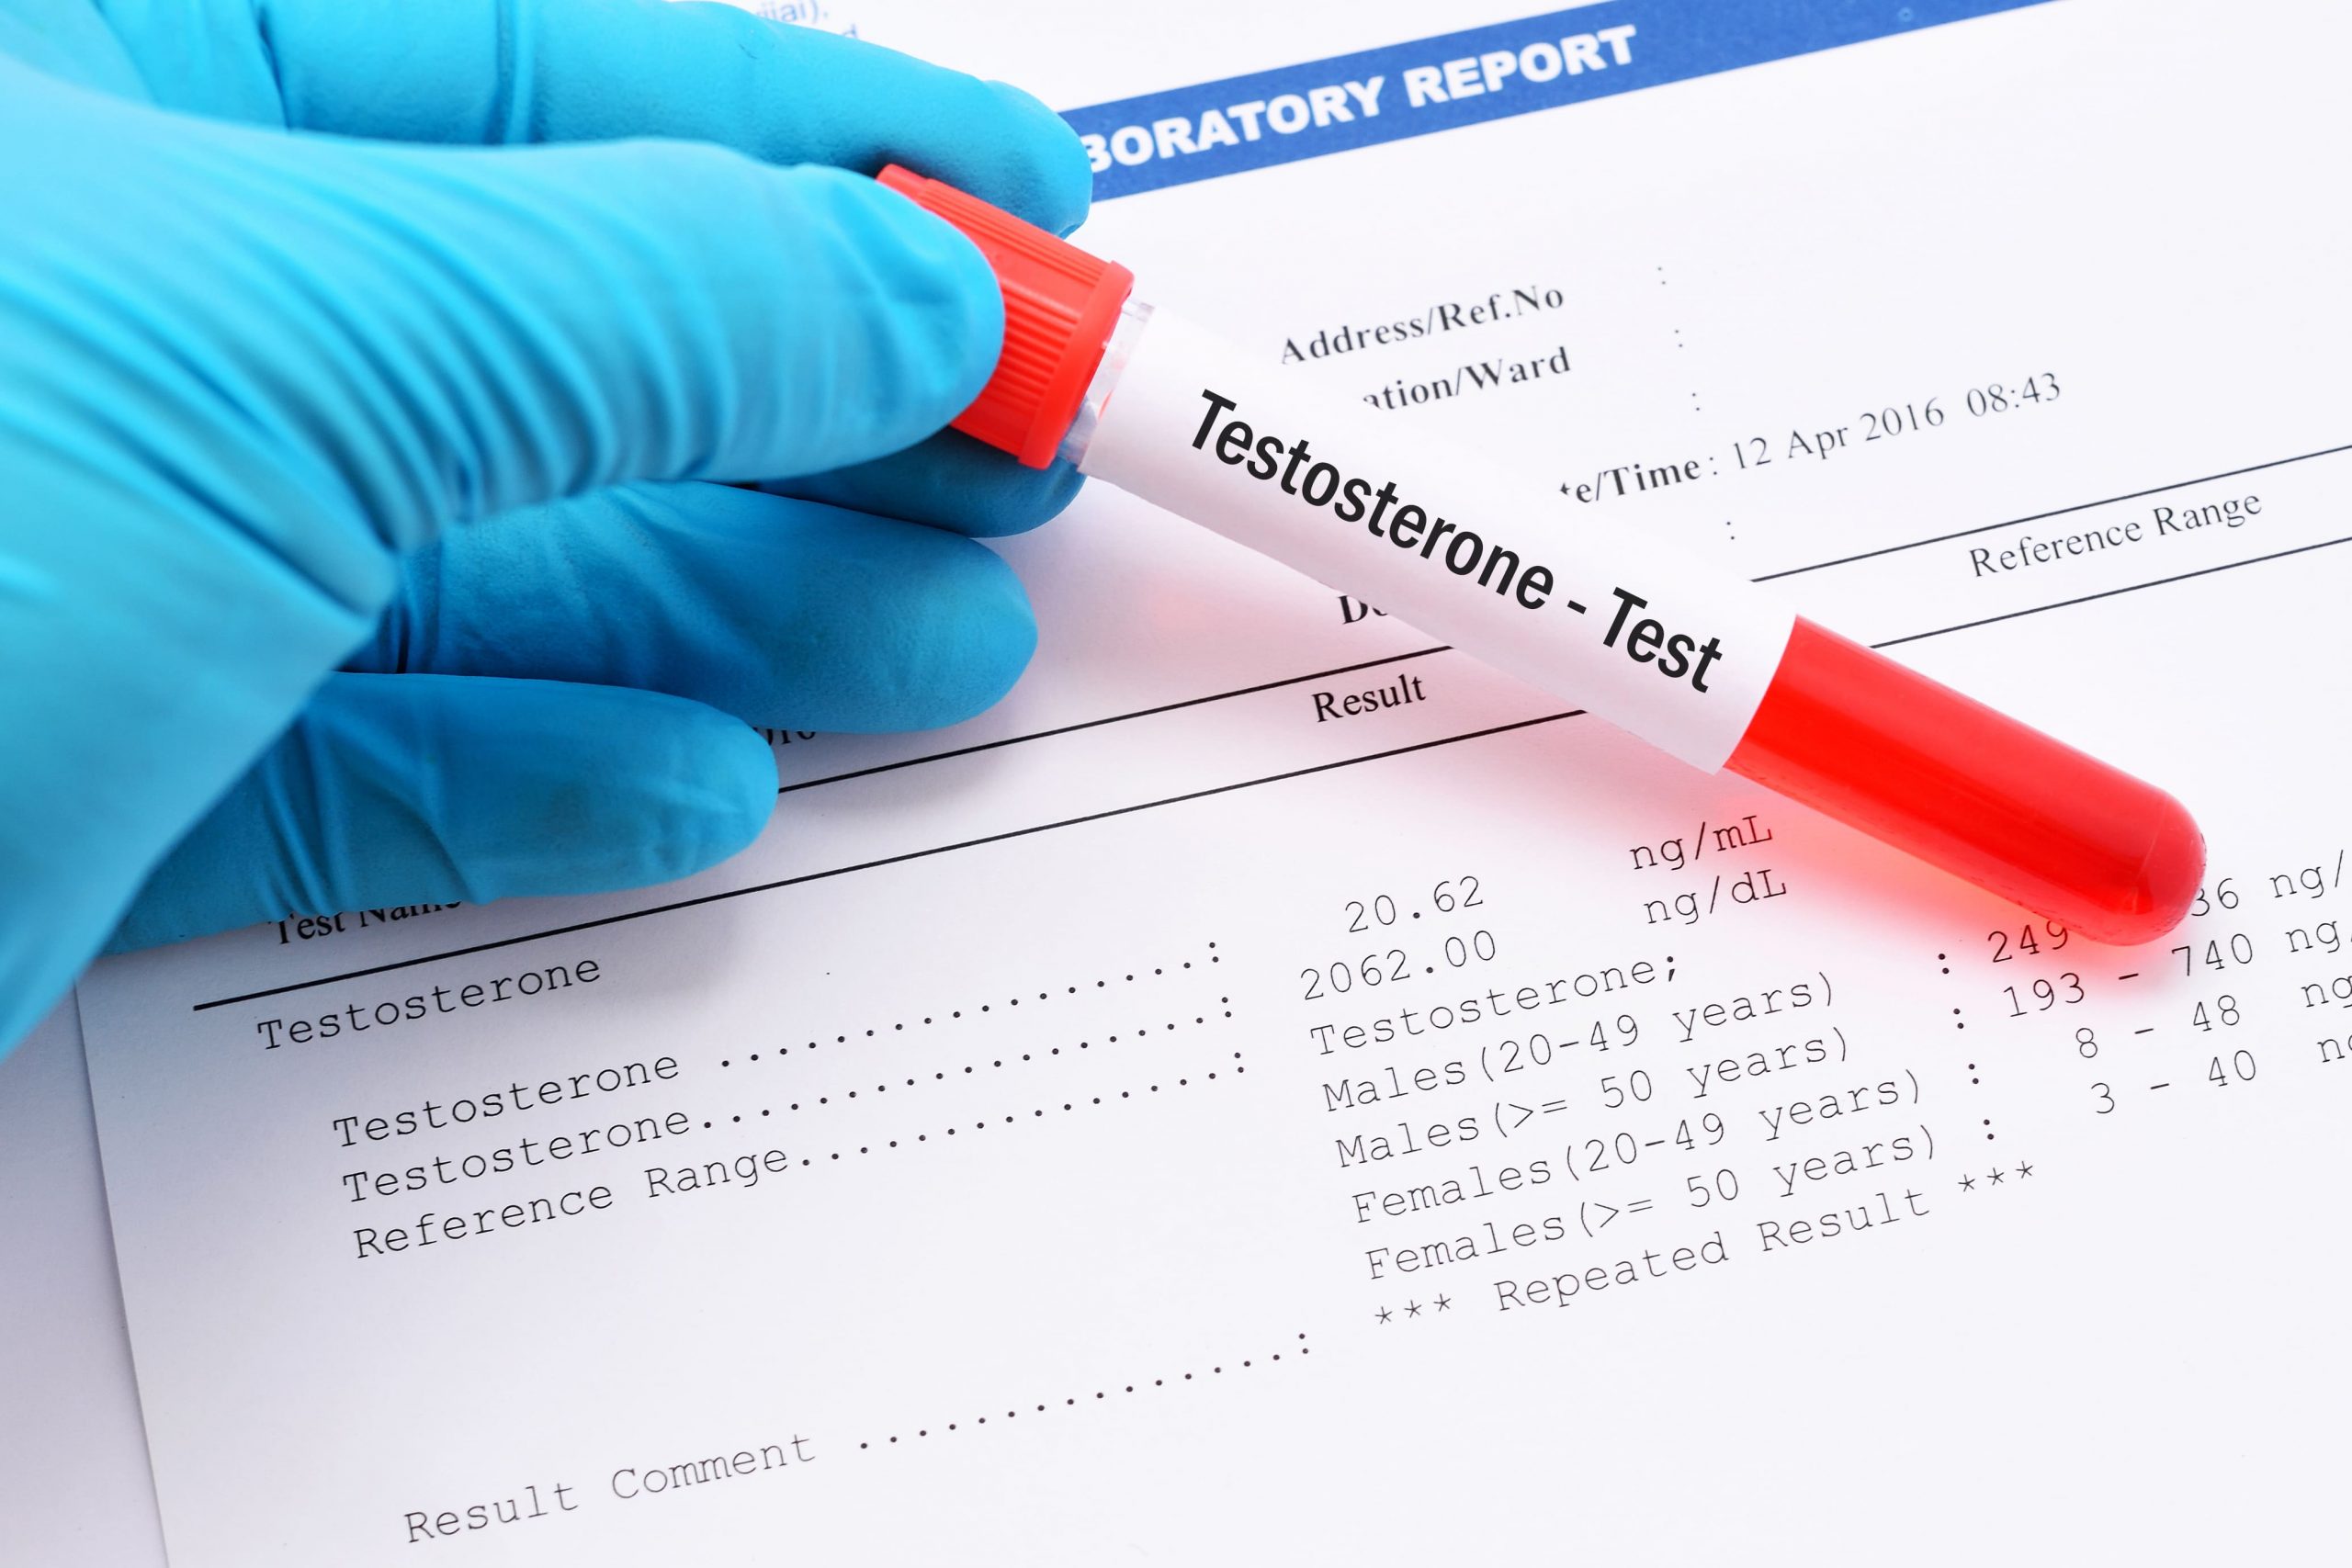

Contact UsSchedule A

Blood Test

Measuring hormone levels through a hormone blood test is essential in determining if and what hormone deficiency or imbalance is present. A hormone blood test enables our Physicians to ensure all of these important hormones remain equally elevated, balanced and within the optimal range for well being.

All blood testing is completed at your local diagnostic laboratory through a quick 5-10 minute blood draw. The blood draw is best obtained in the morning as 12 hours of fasting is required. The comprehensive male anti aging panel includes the following tests:

Male Hormone Test

- Complete Wellness Profile

- Lipid Profile

- Complete Blood Count

- Estradiol

- PSA

- DHEA

- Free and Total Testosterone

- Thyroid Profile

- IGF-1

Female Hormone Test

- Complete Wellness Profile

- Lipid Profile

- Complete Blood Count

- Estradiol

- Progesterone

- DHEA

- Free and Total Testosterone

- Thyroid Profile

- IGF-1